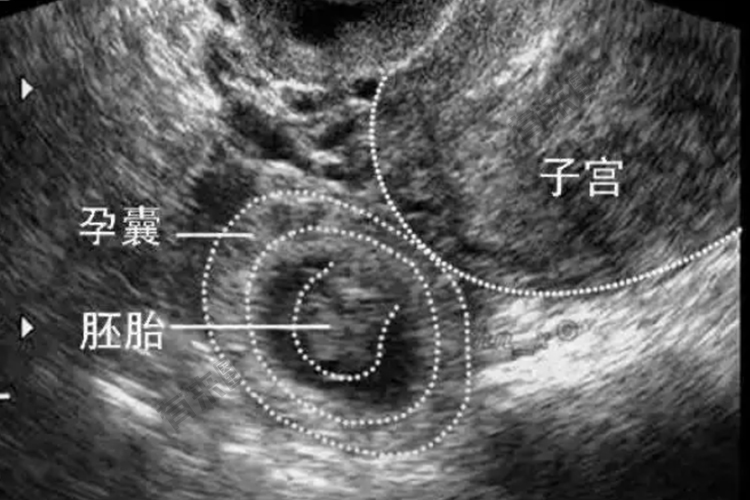

临床表现与受精卵着床部位、是否流产或破裂以及出血量多少和时间长短等有关。在输卵管妊娠早期,若尚未发生流产或破裂,常无特殊的临床表现,其过程与早孕或先兆流产相似。输卵管妊娠出现阴道流血症状占60%~80%。胚胎死亡后,常有不规则阴道流血,色暗红或深褐,量少呈点滴状,一般不超过月经量。

先兆流产是自然流产的一种类型,根据病史及临床表现多能确诊。仅少数需行辅助检查包括超声检查;血、尿hCG测定;孕酮测定等。

输卵管妊娠未发生流产或破裂时,临床表现不明显,诊断较困难,需采用辅助检查方能确诊。辅助检查包括超声检查;hCG测定等。输卵管妊娠流产或破裂后,诊断多无困难。